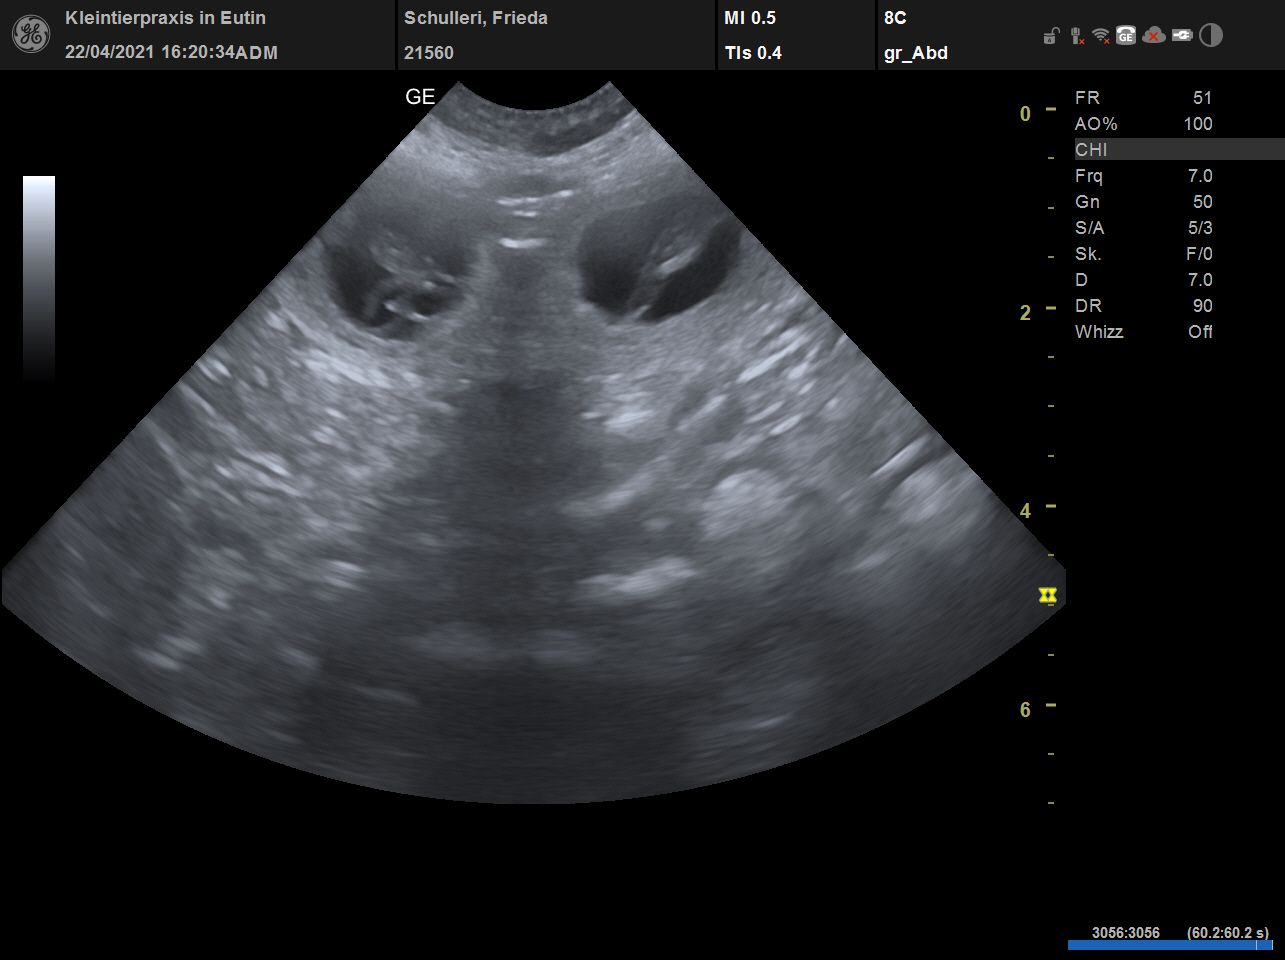

Seit letzter Woche ist es nun gewiss: Frieda erwartet Puppies. Offensichtlich wird es diesmal nur ein kleiner Wurf. Und da es so viele Interessenten gibt, von denen ich schon einige kennengelernt habe, muss ich hier schreiben: